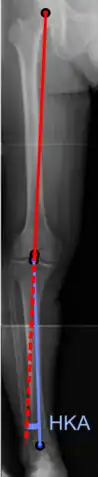

Varus or valgus deformity

There are two disorders relating to an abnormal angle in the coronal plane at the level of the knee:

- Genu valgum is a valgus deformity in which the tibia is turned outward in relation to the femur, resulting in a knock-kneed appearance.

- Genu varum is a varus deformity in which the tibia is turned inward in relation to the femur, resulting in a bowlegged deformity.

The degree of varus or valgus deformity can be quantified by the hip-knee-ankle angle,[33] which is an angle between the femoral mechanical axis and the center of the ankle joint.[34] It is normally between 1.0° and 1.5° of varus in adults.[35] Normal ranges are different in children.[36]

- Hip-knee-ankle angle by age, with 95% prediction interval.[36]